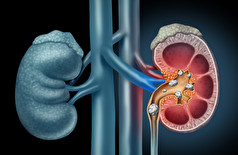

- ابداع یک درمان اساسی برای سنگ کلیه